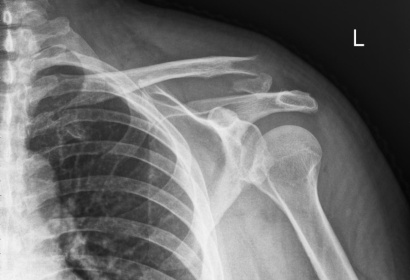

Clavicle Fracture Repair with Plate and Screws